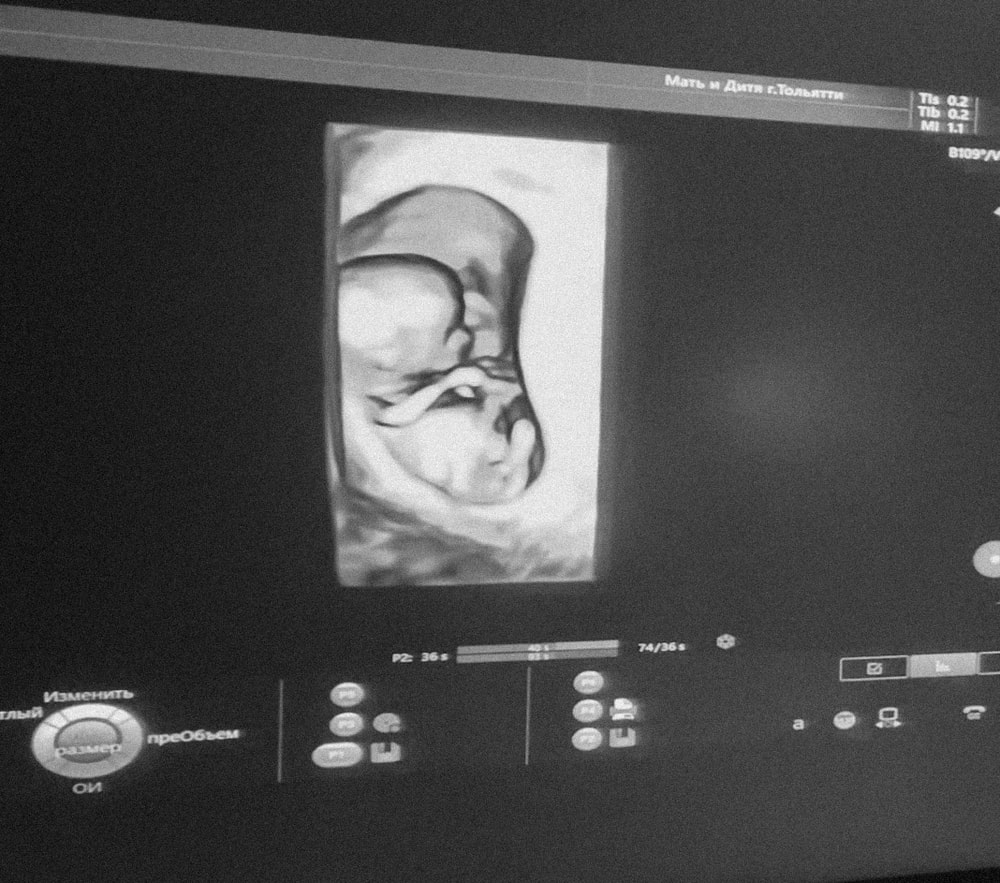

1 скрининг. 12 недель 🤰

Сегодня ровно 12 недель. По УЗИ все хорошо 🙏🏼 Жду результат анализа крови.

Как здорово🥰 даже в 3д дали фотку сделать,или это 4д😅